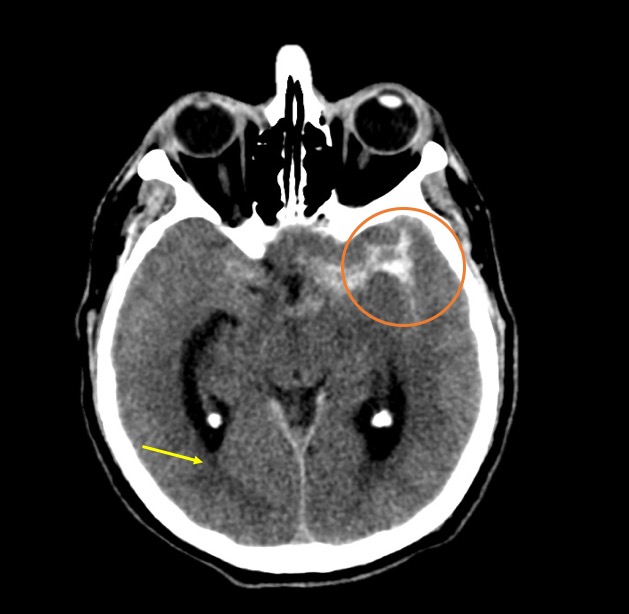

Fig. 1. TC de cerebro sin contraste: corte axial, evidenica HSA Fisher IV, Mayor espesor de HSA con hematoma asociado a nivel del valle Silviano izquierdo (circulo naranja). Volcado hemático ventricular en astas posteriores de ventrículos laterales (ver flecha).